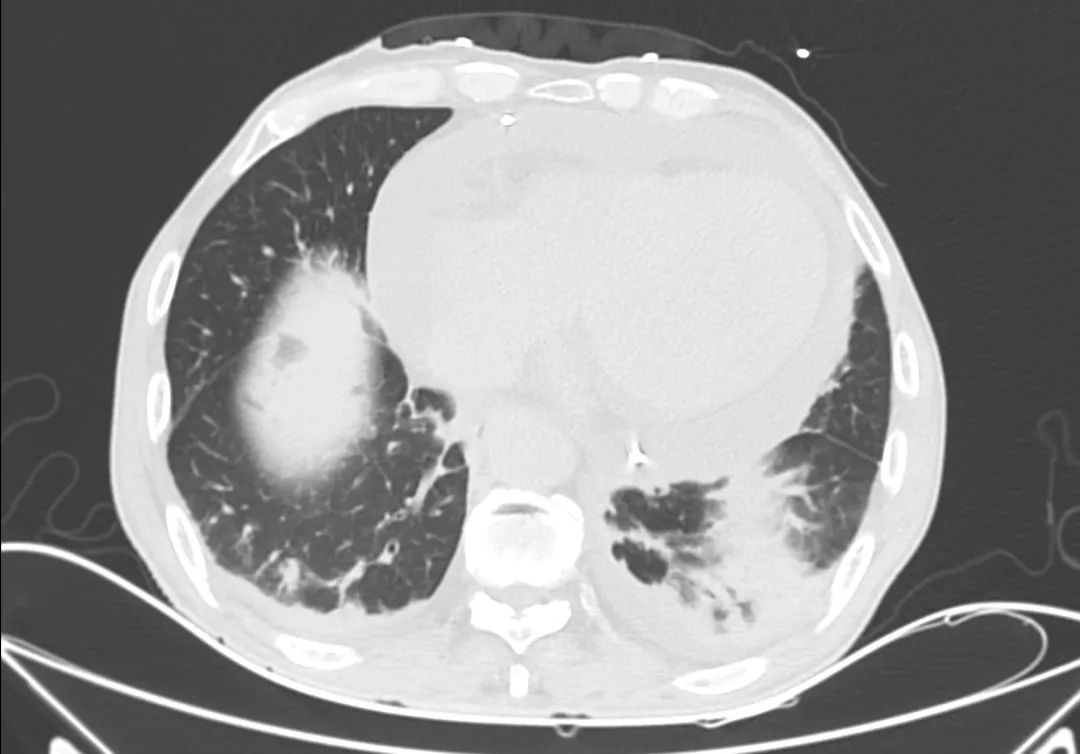

胸部CT

主动脉根部CT断层

根部角度/瓣环/左室流出道

瓣上结构2,4,6,8,10,12mm

SOV/STJ/AAO

左冠风险评估